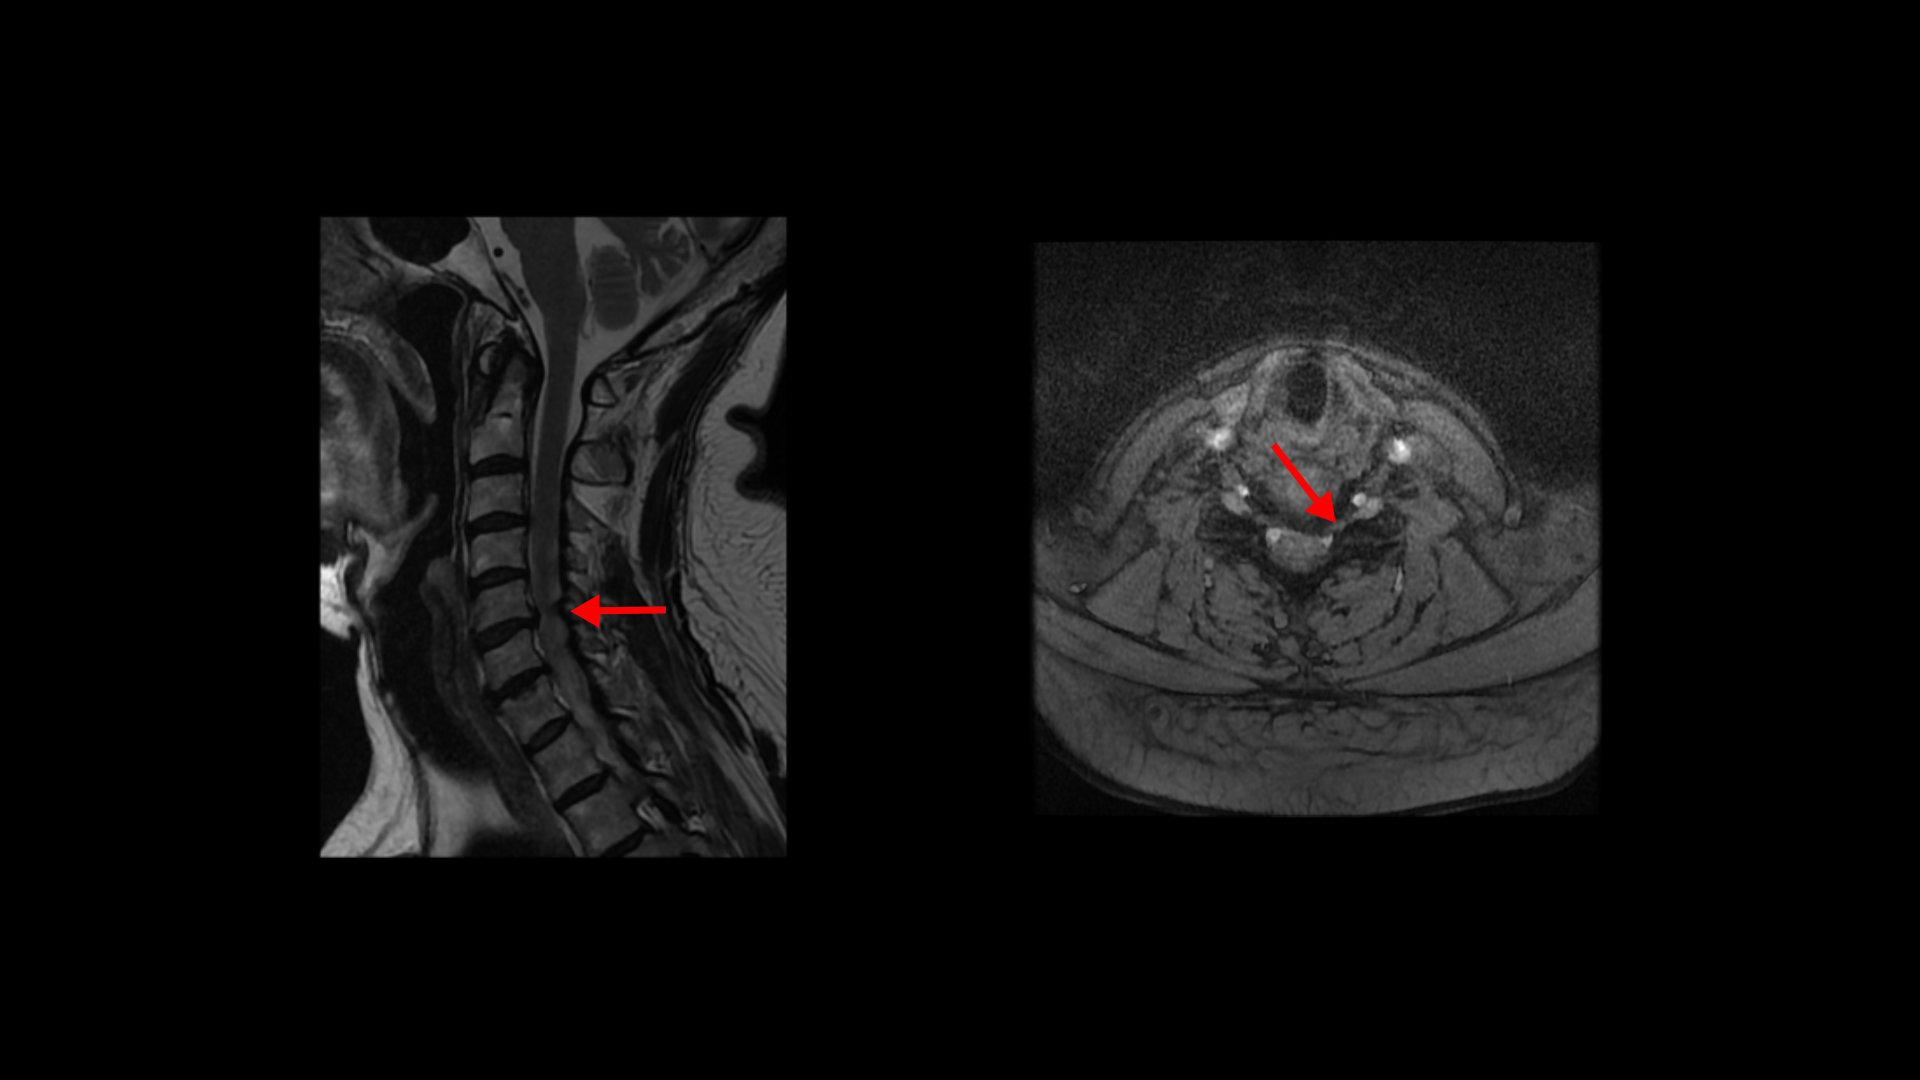

제가 먼저 이 환자분의 상태에 대해 설명드린 후 이분 말씀 더 들어보겠습니다. 이 환자분은 정말 오래된, 본인 표현으로는 30년된 심한 여러 마디의 목디스크와 또 허리에는 2마디의 퇴행성 디스크 및 추간공협착이 있습니다. 목디스크는 MRI로 보면 3번 4번 목디스크가 뼈가 심하게 자라면서 밀려나와있고 왼쪽으로 나가는 신경길을 막고 있습니다.

5번 6번 디스크도 왼쪽으로 심하게 밀려나와 있습니다. 이분 왼쪽 팔의 힘 빠짐 증상은 이것 때문인 것으로 보입니다.